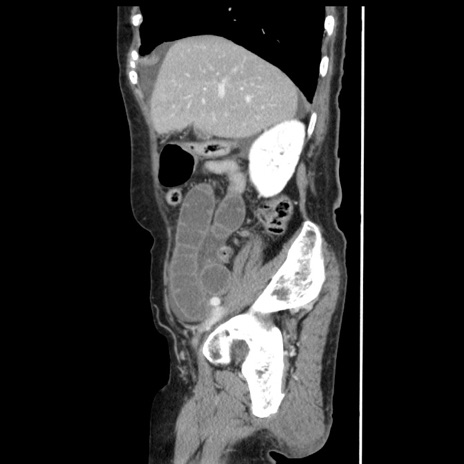

症例1(矢状断像)

【症例】80歳代女性

【主訴】腹痛

【現病歴】8時間前から腹痛あり来院。

【既往歴】糖尿病、脂質異常症、子宮体癌にて子宮全摘術

【身体所見】意識清明・会話良好だが腹痛で苦悶様、全腹部にわたって反跳痛と圧痛あり

【データ】WBC 13600、CRP 0.14、LDH 224、CK 90